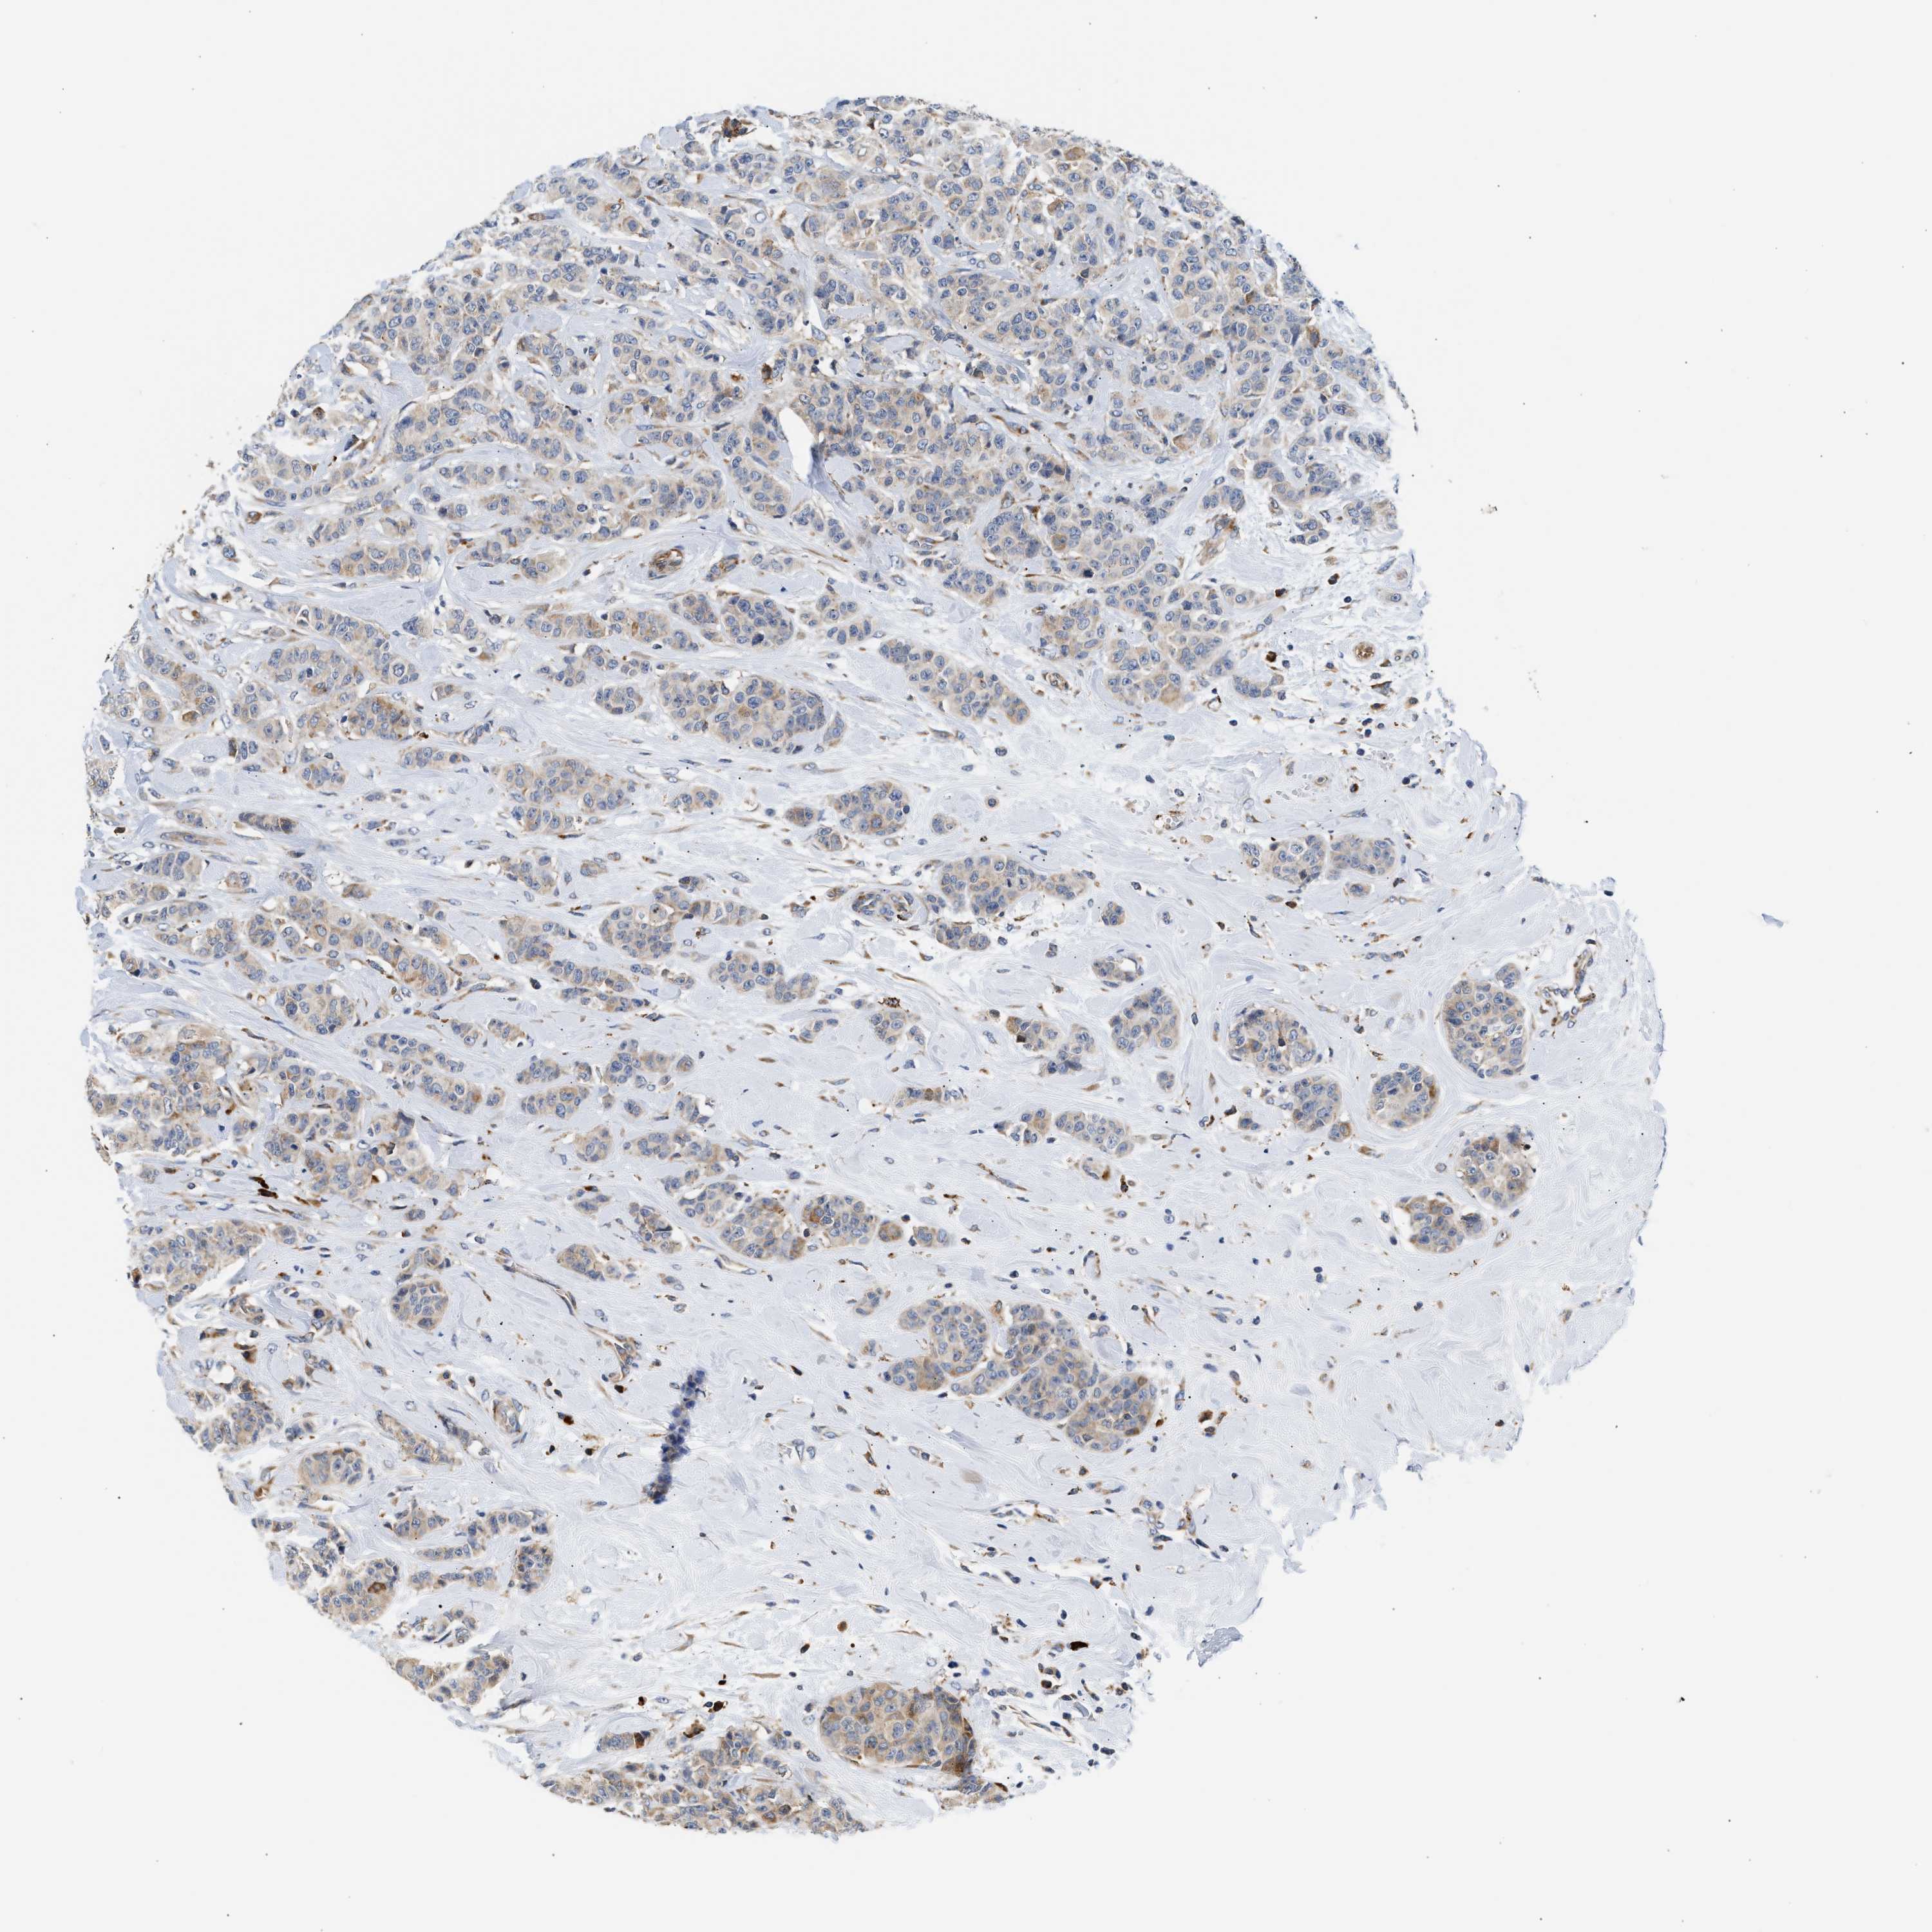

CANCER BREAST CANCER Show tissue menu

BRCA TCGA BRCA VALIDATION PROTEIN EXPRESSION

Breast cancer

Human cancer

AMZ1 is not prognostic in Breast Invasive Carcinoma (TCGA)

Average pTPM 1.6

Number of samples 1022